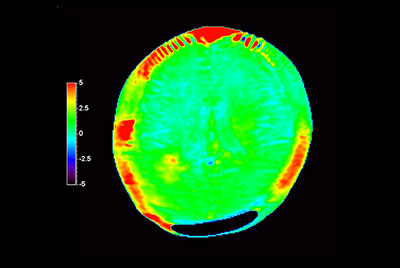

Total Torso with SmartShim